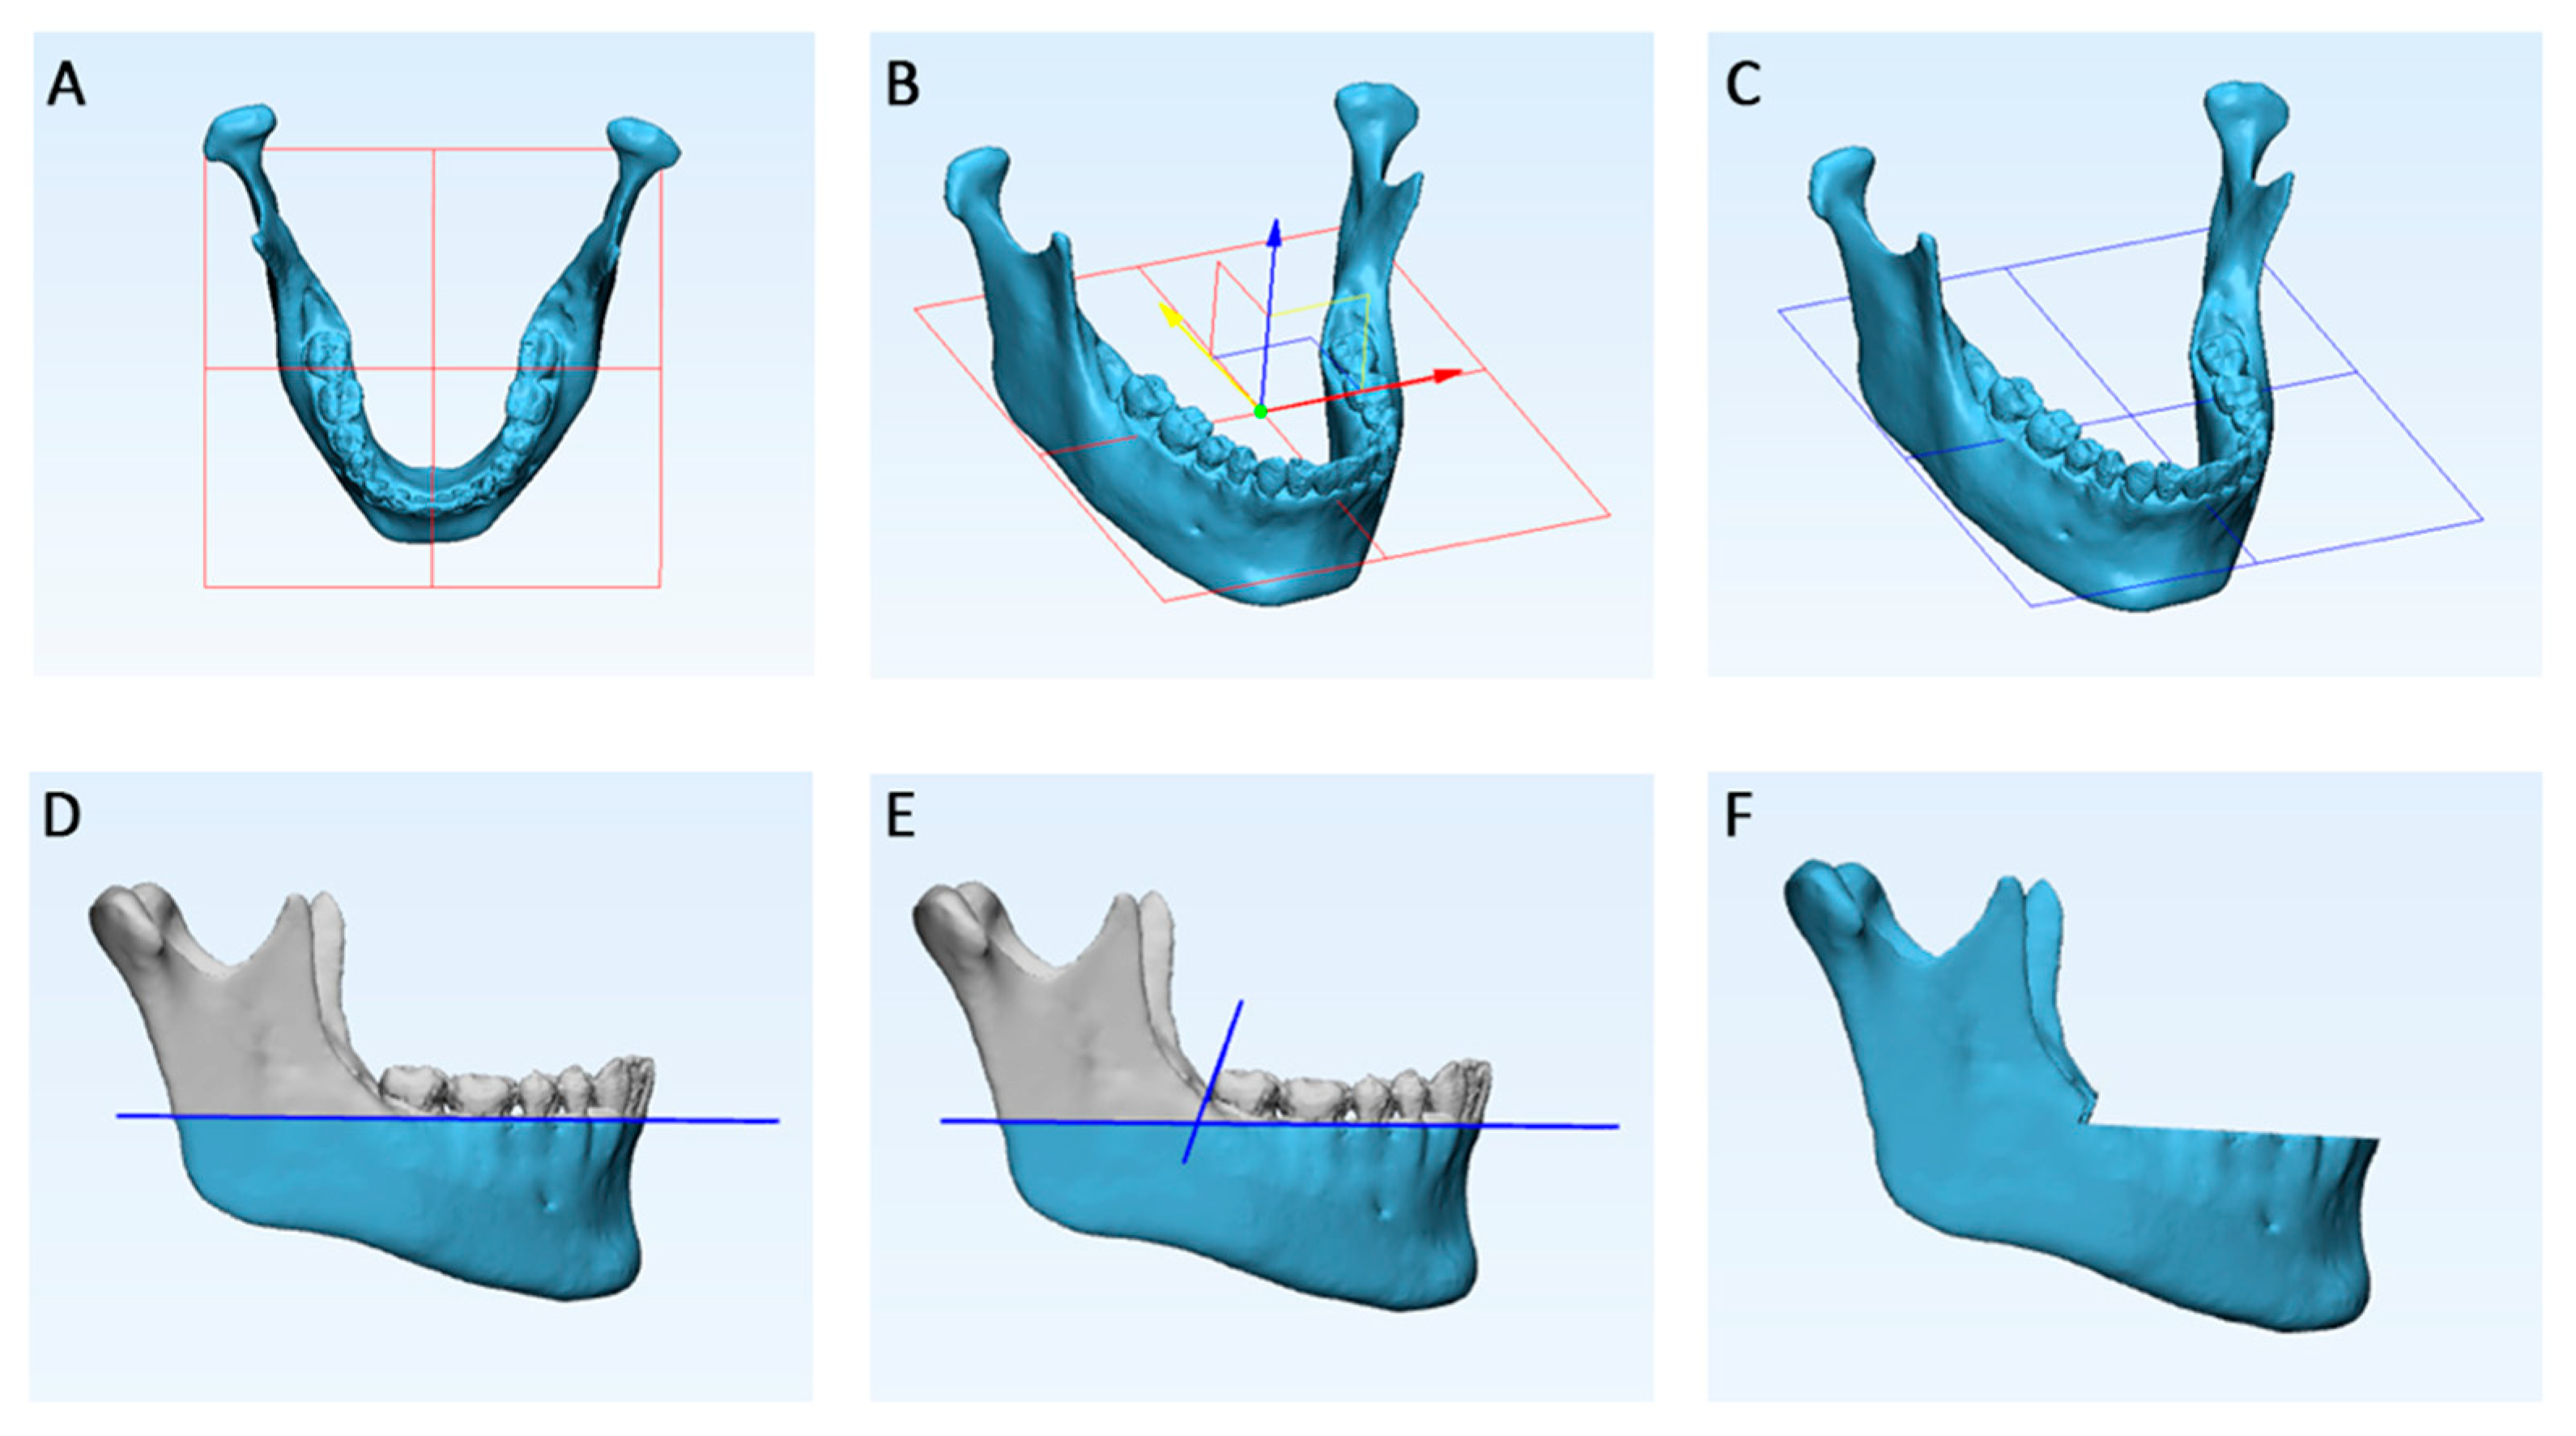

2. Materials and Methods